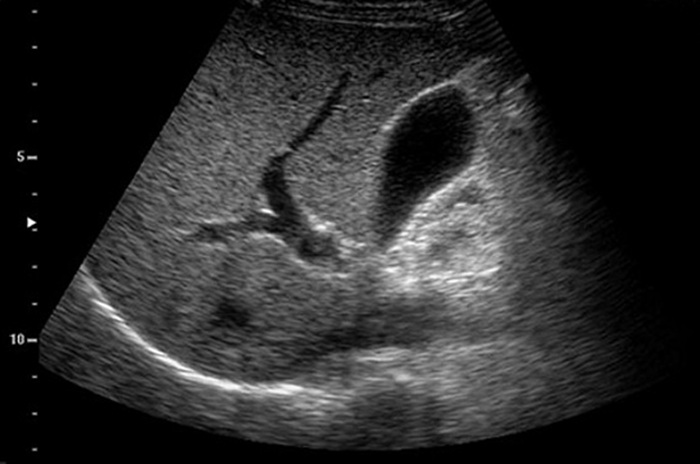

Во время исследования врач функциональной диагностики изучает состояние органов и протоков, вен и сосудов. Определяет размеры, их структуру, после чего, сравнивает эти показатели с нормами здорового человека. Полученные данные описывает в заключении и отдает пациенту. Следует помнить, что для постановки точного и достоверного диагноза необходимо тщательное обследование, которое подтвердит или опровергнет наличие патологии.